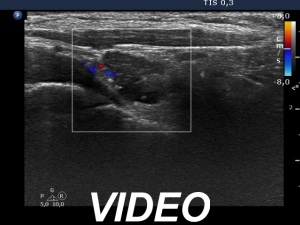

Ultrasound. Connective tissue replaced the thyroid parenchyma in both thyroid beds. There was a hypoechoic mass in the lower part of the right thyroid bed dorsal to the carotid artery. The lesion was a mixed, dominantly solid nodule and had microcalcifications.

Aspiration cytology from the hyperechogenic lesion resulted in papillary cancer. Wash-out thyroglobulin was 6905 ng/mL